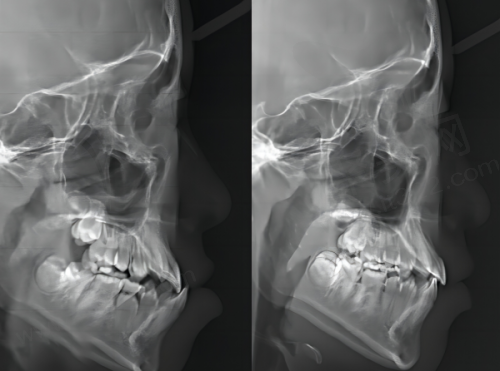

硬件设备:医院配备了精良的设备,像CBCT、数字化口扫仪、种植导航系统等。这些设备能支持即刻种植、隐形矫正等精细化治疗,满足大多数患者的复杂需求。

医生背景:医院里的医生主要是执业年限10年以上的主治医师,部分医生还有国有医院从业经历,他们的资质都能在卫健委官网查到。在种植和正畸领域,还有细分的骨干医生,比如擅长复杂骨增量种植、青少年错颌矫正的医生。

技术特色医生举例:像张本文医生,擅长All - on - 4和即刻负重技术。他凭借丰富的临床经验,能为患者提供专精的诊疗服务,帮助特别多患者解决了牙齿问题。